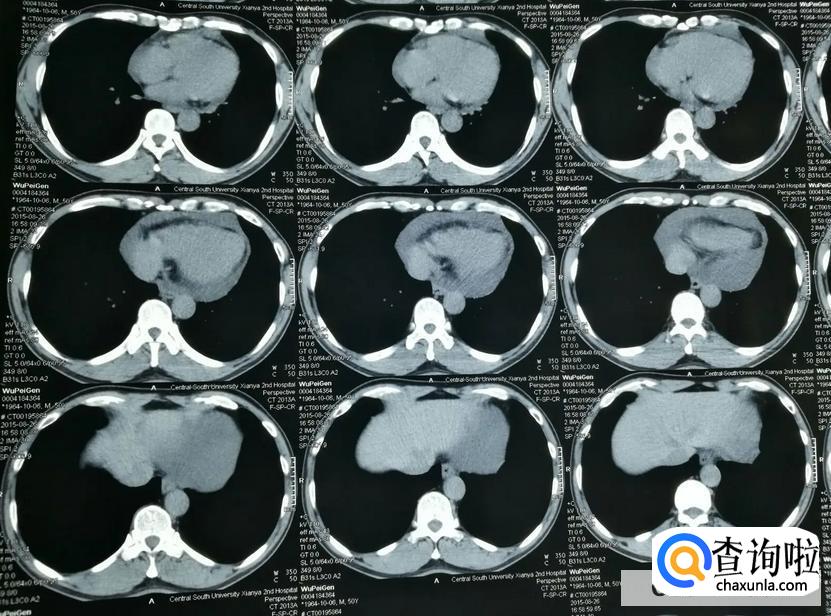

心脏心包积水又被称之为心包积液,它产生的主要症状为急性心包填塞症状。一般表现为循环衰竭。当发生急性的心包填塞时,患者可能会出现心跳过快,脉搏细弱,静脉压升高,动脉压下降。要是情况比较严重的话,很有可能会出现休克的状态,当然还会伴随大汗,心跳快,血压低,甚至,测不出具体的情况。

目前心脏心包积水主要分为急性心包积液和慢性心包积液,其中急性心包积液严重程度取决于积液形成的速度。

一旦出现以后,需要紧急解除心包积液对于心脏的压迫,常见的方式是进行心包穿刺,将积液引出。

而慢性心包积液形成的积液速度是比较缓慢的,因为心脏适应缓慢增加的积液,而心脏症状可能并不是特别的明显。但是长期慢性形成的心包积液可能会使后期回心血量减少,外周淤血情况加重。当然也有一些患者会出现外周浮肿,尤其是下肢。要是患者到了晚期心包积液,可能会有淤血性肝硬化,同时会长期低血压,也会产生众多的危害。